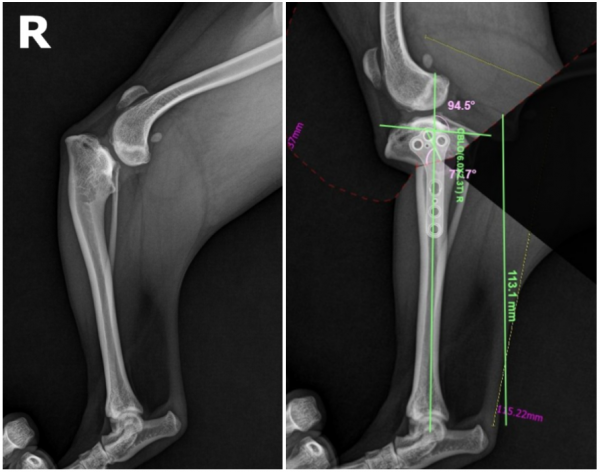

수술 전 계획 수립

-오차 없는 수술을 위해 철저히 계획합니다.

수술 전에는 CT 촬영을 통해 방사선(X-ray)으로는 확인할 수 없는

정교한 뼈 구조와 관절면의 위치를 세밀하게 분석했습니다.

그 결과, 관절면의 접촉 부위가 한쪽으로 치우쳐 있는 것도 확인되었습니다.

이후 예비 수술 프로그램을 이용해

가상의 환경에서 실제 수술을 시뮬레이션하며

안전하고 정확한 수술 계획을 세웠습니다.

수술 후 영상검사

사실 보기에는 쉬워보여도 주변에 근육과 인대가 많아서

정확히 수술하는 것은 매우 어려웠습니다.

그러나 수술 후 영상검사 시 정확하고 완벽하게 수술이 된 것을 확인할 수 있었습니다.